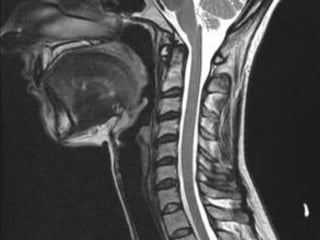

47 year old woman with 6 month h/o neck stiffness and pain with

left UE paresthesias into

The elbow forearm and hand especially IF/thumb

Note:the black line directly posterior to the vertebral bodies and relative

Thinning of spinal cord, note normal disc height

Cephalomedullary angle 135-175